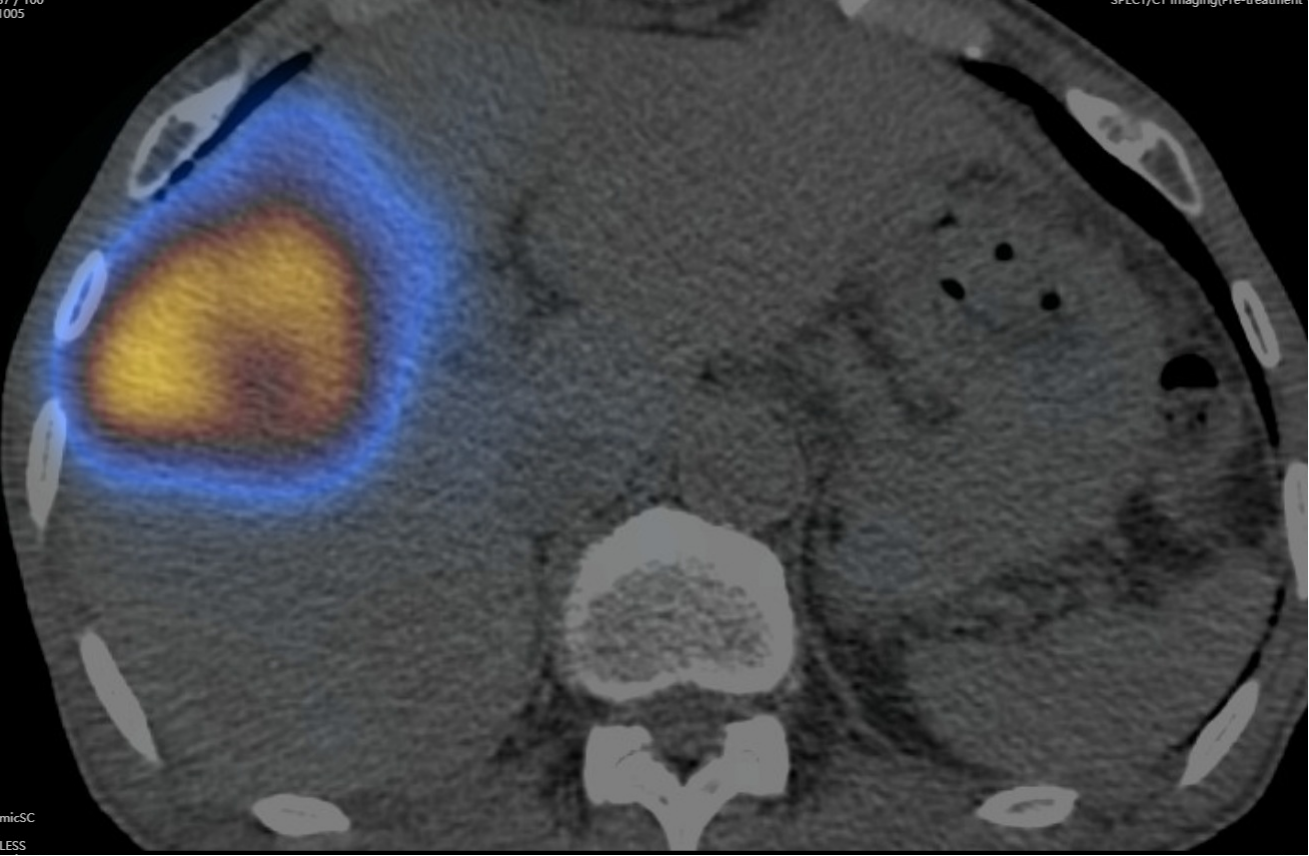

患者术后SPECT/CT显示,核素在病灶区沉积良好

术前及术中,疾控感控办公室协助全面做好接诊空间疫情防控和消杀部署,核医学科、放射科、钇[90Y]中心导管室、留观室、肝胆胰中心医护团队严密防护,历时约四小时顺利完成手术。患者术后SPECT/CT显示病灶部位微球浓聚良好,无肝外微球异常浓聚,患者肝功正常,术后第二日顺利出院。